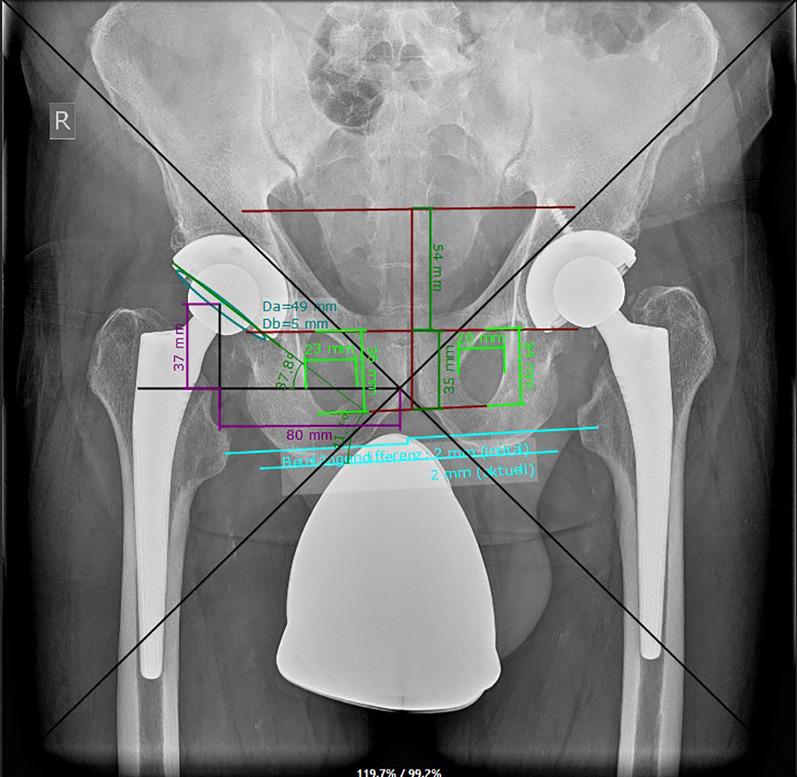

Results: A total of 32 patients (0.45%) experienced liner dislocation at a mean 71.47 ± 60.10 months post surgery. Significant factors contributing to dislocations included the use of a conventional compared with a highly crosslinked polyethylene component (p = 0.049) and screw fixation (p = 0.028). Radiographic and CT analysis highlighted the importance of proper component orientation, revealing that patients experiencing dislocations demonstrated significantly lower acetabular cup anteversion angles (p = 0.001) compared with the control group. Impingement and malposition, identified in 41% and 47% of the cases, respectively, further underscored the multifactorial nature of dislocation risks.

Conclusions: While the overall rate of polyethylene liner dislocation was low, the findings of this study highlight the importance of appropriate cup placement to decrease the risk of dissociation. It further substantiates the influence of impingement and malposition in liner displacement, with increased mechanical stress exerted on the locking mechanism under adverse conditions and the potential risk increase due to screw placement.

背景:用于全髋关节置换术(THA)的模块化髋臼组件具有术中灵活性,但可能会发生聚乙烯衬垫分离。本研究的目的是在一个中心检查与特定髋臼组件设计相关的衬垫解离的发生率和原因:对7027名接受初级THA的患者进行回顾性分析,以确定孤立的衬垫脱位。分析了患者的人口统计学特征、临床表现、手术和植入物细节,以及X光和计算机断层扫描(CT)结果。通过2:1倾向得分匹配法将衬垫脱位患者与对照组进行匹配,并采用逻辑回归分析确定相关风险因素:共有32名患者(0.45%)在术后平均71.47 ± 60.10个月出现衬垫脱位。导致脱位的重要因素包括使用传统聚乙烯组件(p = 0.049)和螺钉固定(p = 0.028),而使用高交联聚乙烯组件(p = 0.049)和螺钉固定(p = 0.028)。X光片和CT分析强调了组件正确定位的重要性,显示与对照组相比,脱位患者的髋臼杯反转角度明显较低(p = 0.001)。在41%和47%的病例中分别发现了撞击和错位,这进一步强调了脱位风险的多因素性质:虽然聚乙烯衬垫脱位的总体发生率较低,但本研究结果强调了适当的髋臼杯置入对降低脱位风险的重要性。它进一步证实了撞击和位置不正对衬垫脱位的影响,在不利条件下锁定机制受到的机械应力会增加,螺钉置入可能会增加风险。